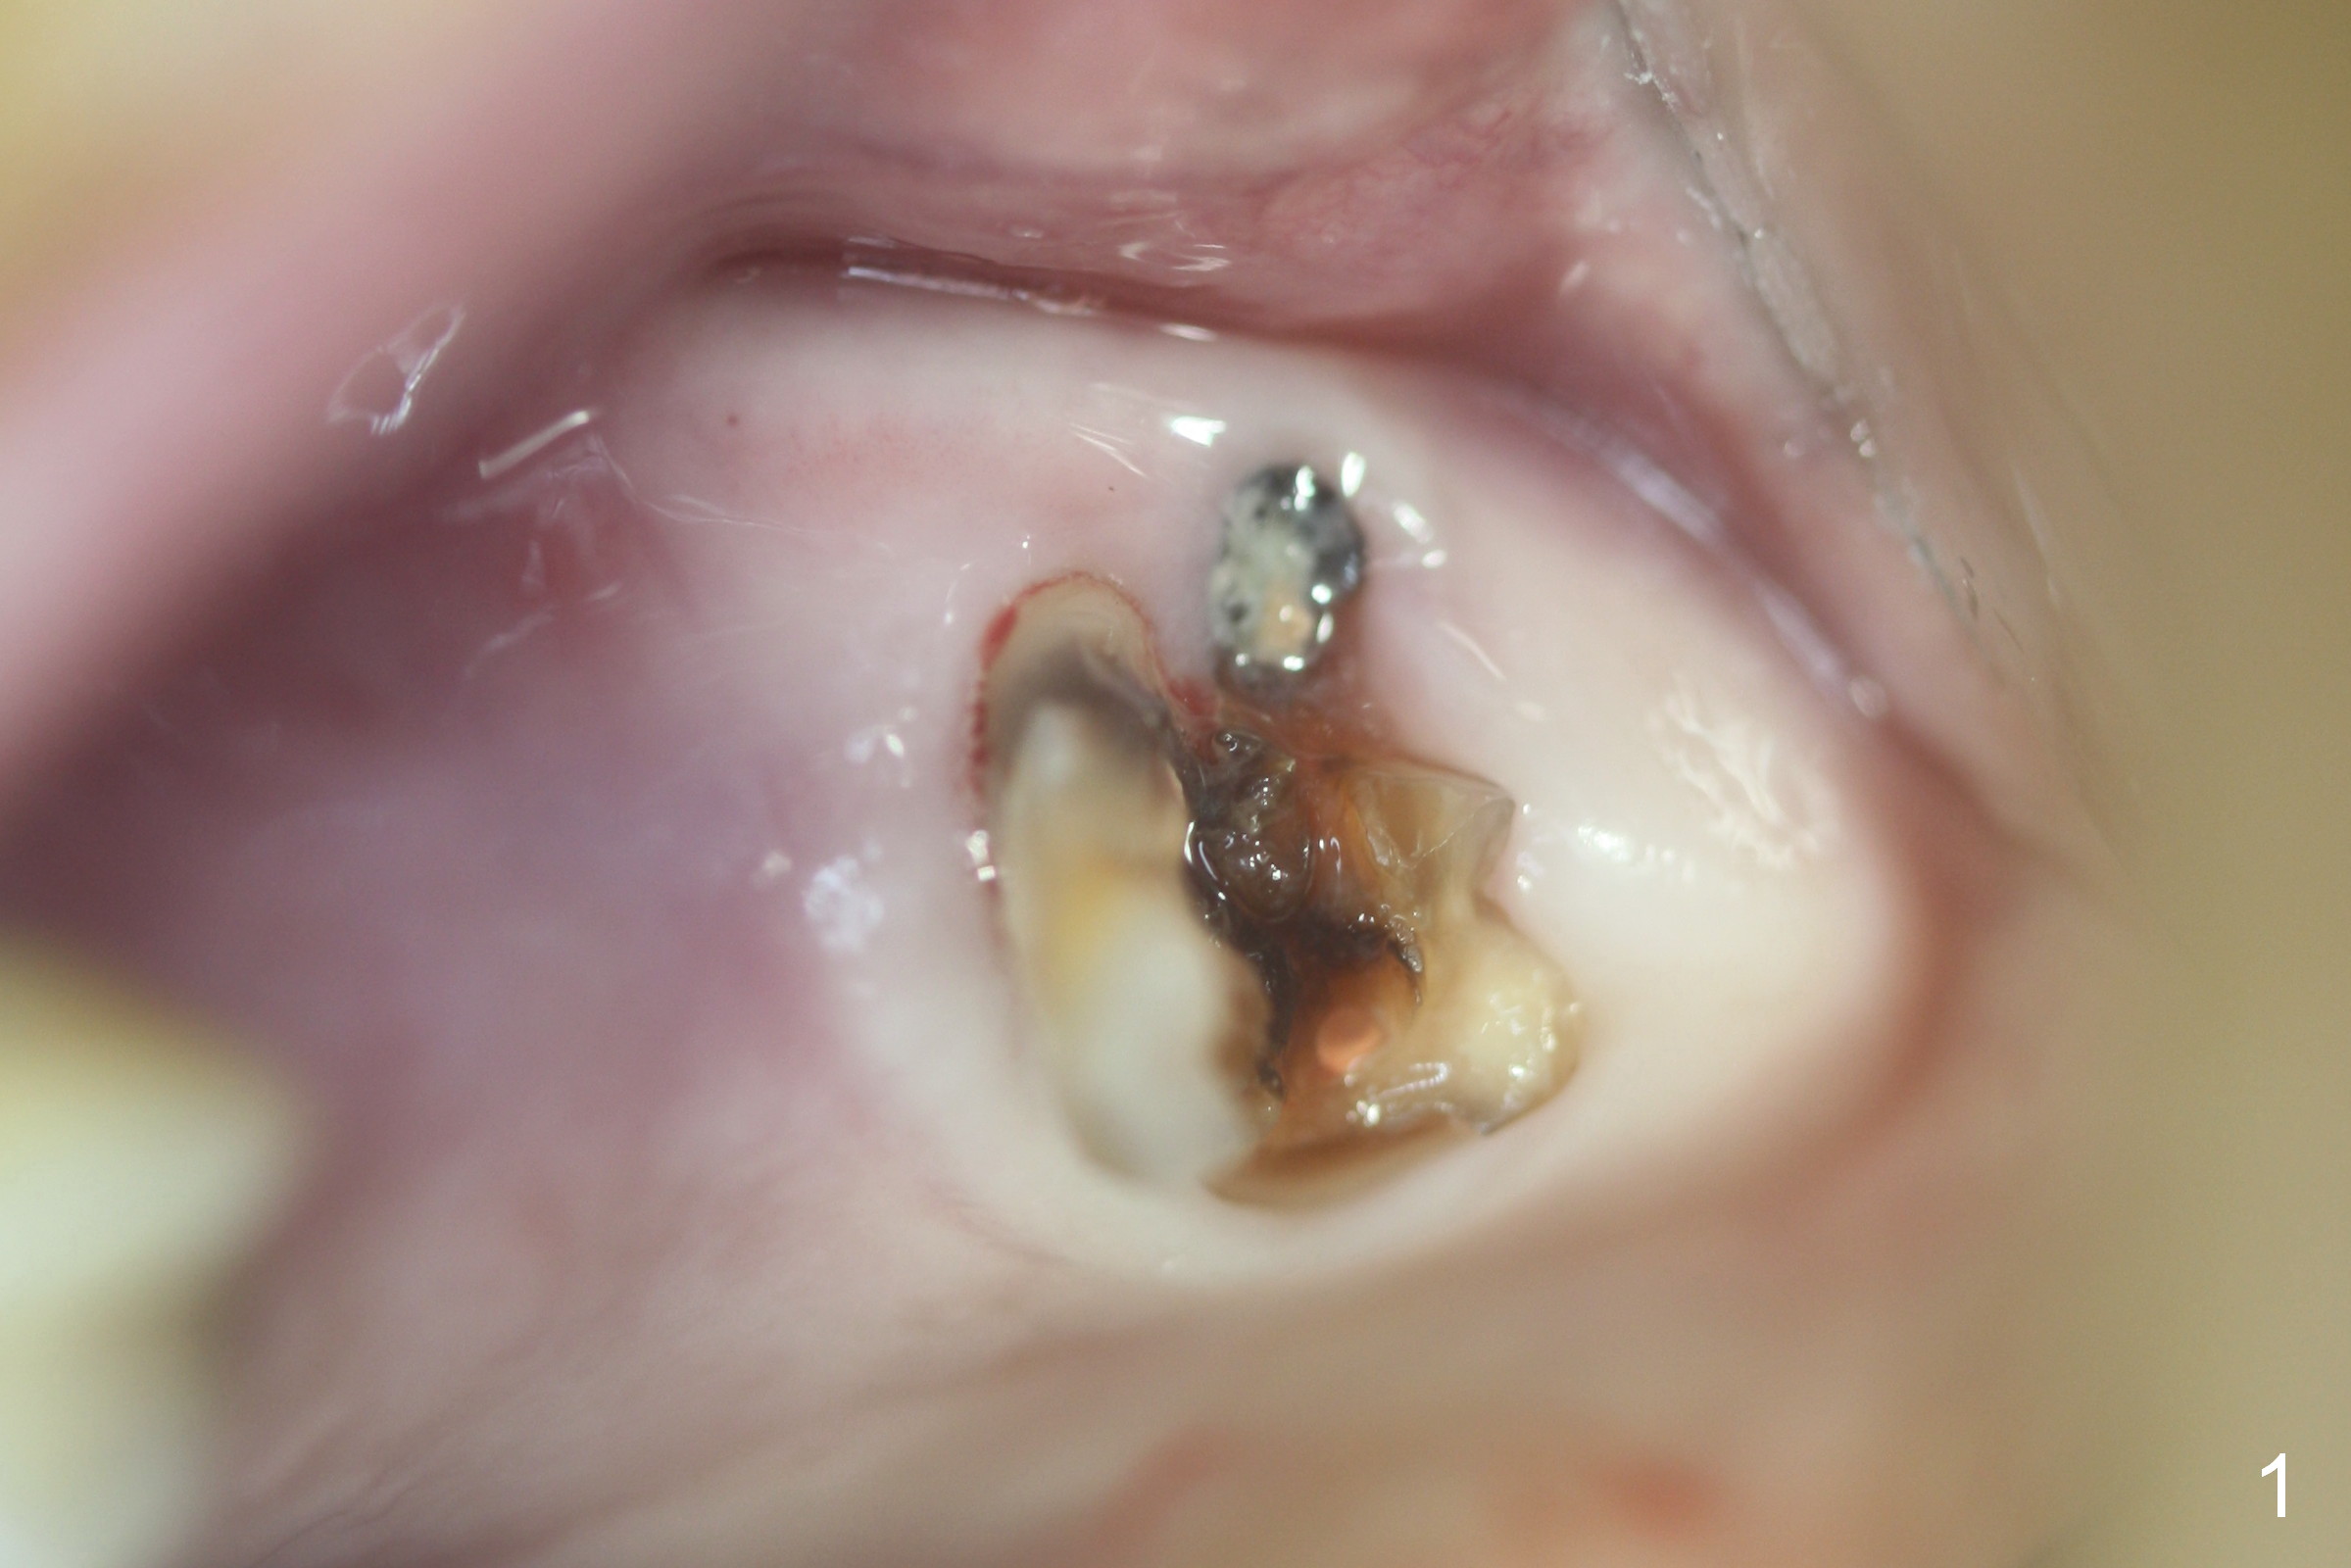

Fig.1,2 show the close relationship of the upper flipper and the residual roots at #15. Atraumatic extraction using periotomes and surgical sectioning still results in perforation of the mesiobuccal socket (Fig.3 >). The distobuccal one is shallow, while the septum is small. It appears that the palatal (Fig.3 P) socket is the most ideal recipient site for the immediate implant and is expanded with Magic Osteotomes until 4.3 mm (Fig.4,5) with the coronal end pushed as buccal as possible. After placing allograft for sinus lift (Fig.6 >), a 5x11 mm IBS implant is placed with insertion torque ~ 50 Ncm. A 6x4(3) mm pair abutment is placed, followed by bone graft in the remaining sockets (Fig.6 *) and by Osteogen plug (Fig.7 *). Finally the socket is sealed by applying acrylic over the abutment (Fig.8). While the acrylic is setting, the flipper is seated and excess acrylic is removed and pushed away from the flipper (Fig.9). Advise the patient not to wear the flipper. If it is being worn, there will be minimal contact between the flipper and the immediate provisional.